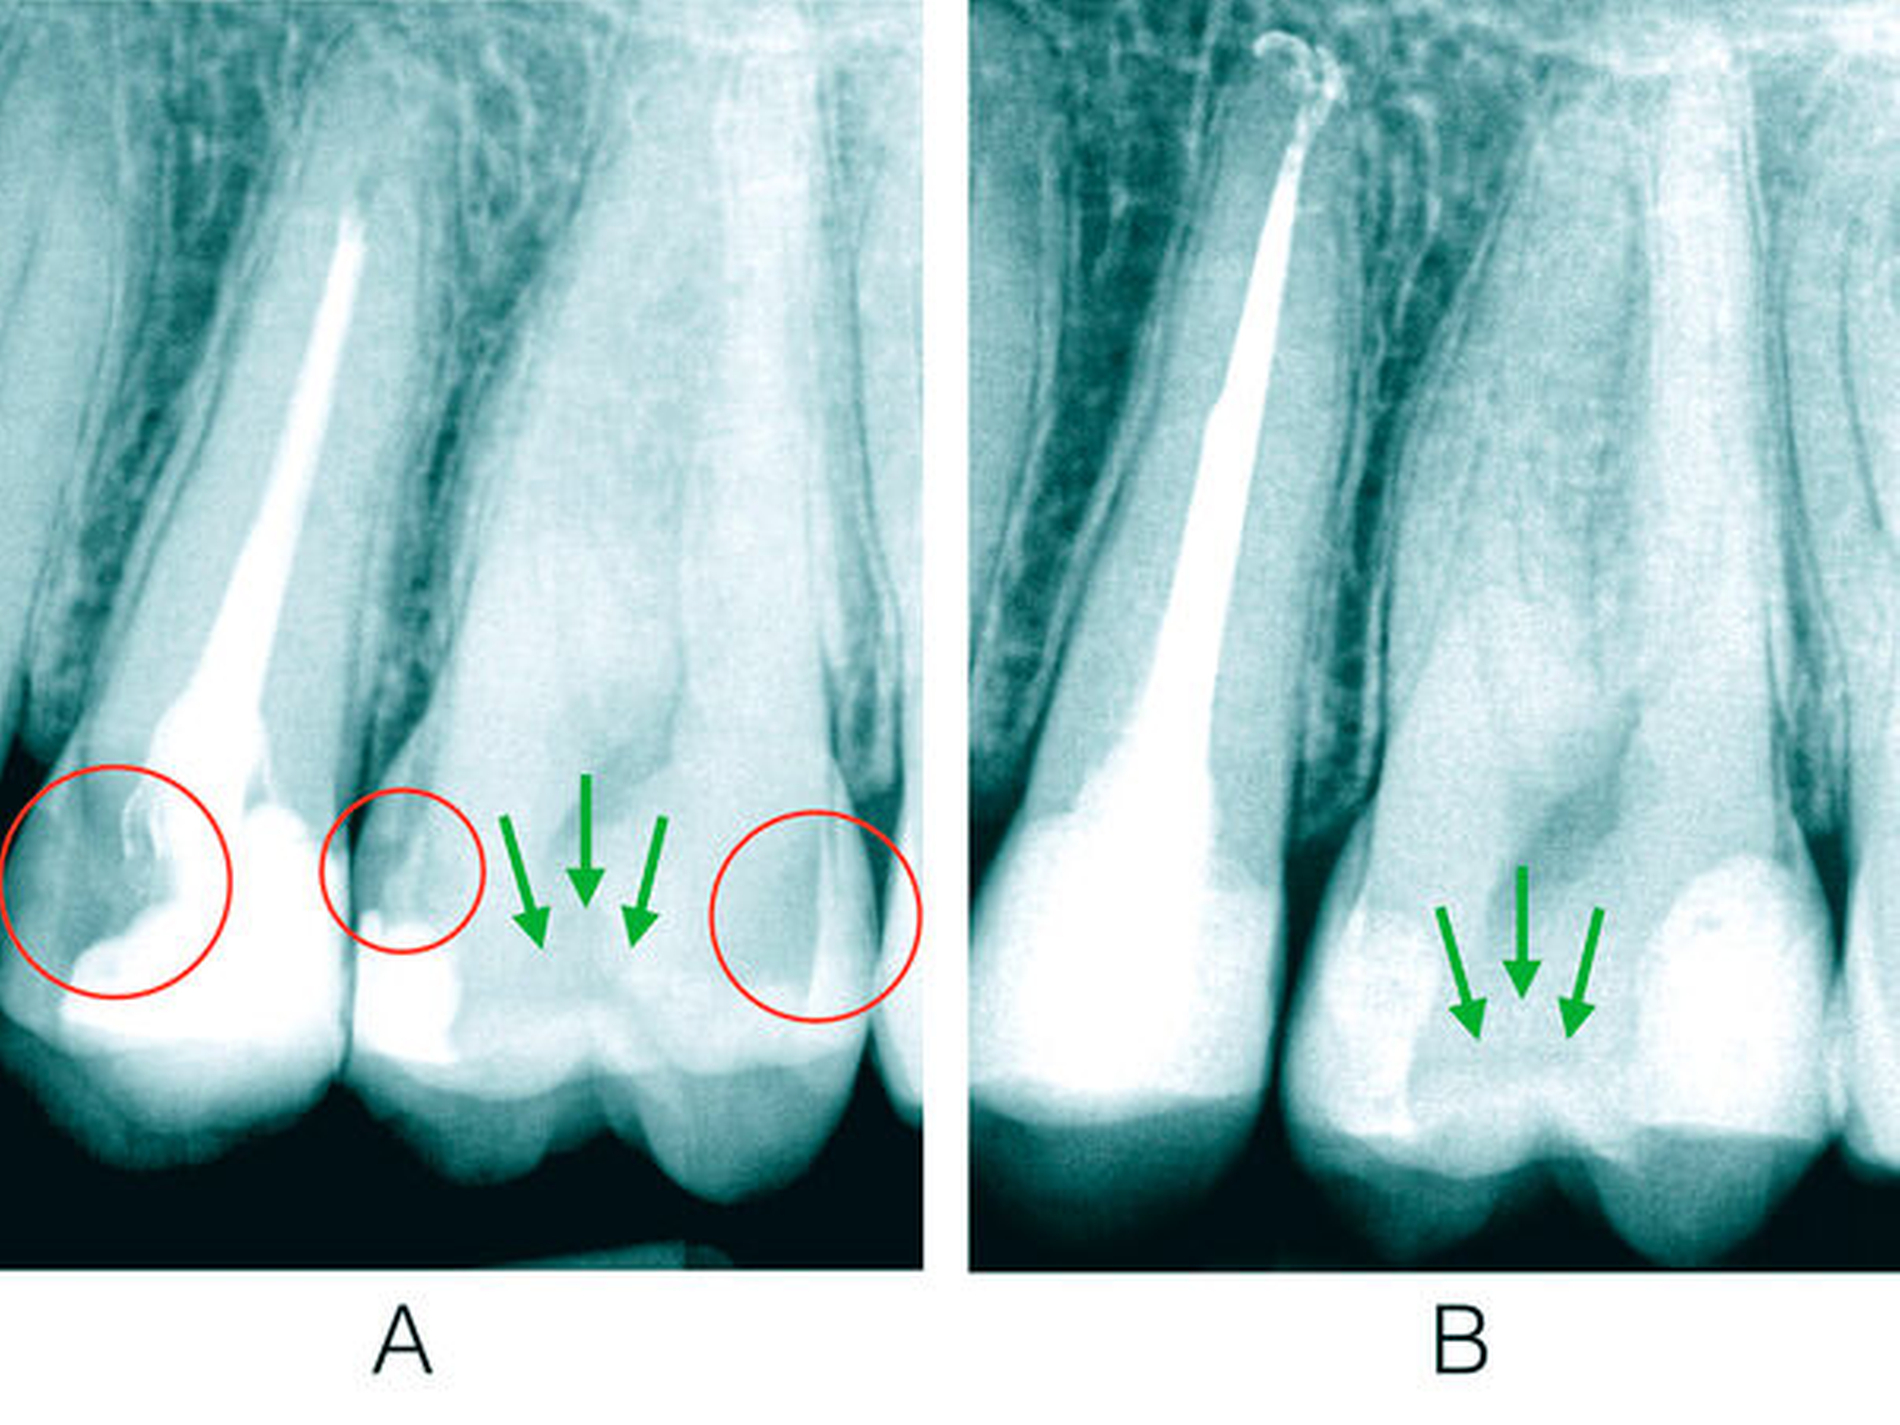

Ein 34-jähriger Patient stellte sich im August 2020 zur Wurzelkanalbehandlung an 25 und 36 und zur Versorgung kariöser Läsionen an mehreren Zähnen in der Praxis vor. Die Anamnese und der bisherige Therapieverlauf offenbarten eine hohe Kariesaktivität ab dem 25. Lebensjahr. An Molar 26 wurde klinisch und radiografisch eine profunde Karies mit deutlicher Progression mesial und distal diagnostiziert (Abbildungen 1 und 4). Gleichzeitig war der Zahn durch eine frühkindliche, metabolisch ausgelöste Hypoplasie von Schmelz und Dentin geprägt. Die Inzisivi und die unteren Molaren waren von der Anomalie nicht betroffen, stattdessen zeigten sich hypoplastische weiße Flecken an 31, 32 und 33 (Abbildung 1). Der Zahn 16 war im Alter von 21 Jahren alio loco extrahiert worden.

Nach Eröffnung der distalen Läsion an 26 wurde im vollständig kariesfreien hypoplastischen Dentin aus der präeruptiven Zahnentwicklung eine typische ausgedehnte hypermineralisierte Transparenzzone freigelegt. Die Dentinkaries wurde konventionell mit einer Unterfüllung als Pulpaschutz („Dentinersatz“) versorgt und mit Composite-Material („Schmelzersatz“) aufgebaut. Weil die Hypoplasie-Areale auch nach knapp zehn Jahren hoher Kariesaktivität nicht befallen waren, blieben diese Areale selbst an den Kavitätenrändern unversorgt (Abbildung 2).

Diese Dentin-Hypoplasie reagiert durch überlebende Odontoblasten mit einer heftigen Hypermineralisation als Dentinsklerose, die sich während der Eruption, in der eine kurzzeitige Hypersensibilität entstehen kann, weiter ausbreitet und parallel zur früheren Schmelz-Dentin-Grenze verläuft [Berten, 1895] (Abbildung 2b). Entsprechend dem Invaginationskonzept im Glockenstadium [Gängler, 1986] entstehen dann runde hypoplastische Schmelzwülste an den Rändern der Aplasie [Ida-Yonemochi et al., 2020], wie in diesem Fall bei dem Molaren. Diese bleiben ebenso kariesresistent wie das Dentin und können in jedem Lebensalter minimal-invasiv an Restaurationen erhalten bleiben (Abbildung 2c).